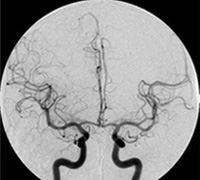

¢£ ·ì´É»£±Æ¸¡ºº

·ì´É»£±Æ¤È¤Ï¡¢¥«¥Æ¡¼¥Æ¥ë¤È¸Æ¤Ð¤ì¤ëºÙ¤¤´É¤òÁÍ·ÂÉô¤äÏӤʤɤ«¤é·ì´ÉÆâ¤ËÁÞÆþ¤·¡¢Â¤±ÆºÞ¤òÃíÆþ¤¹¤ë¤³¤È¤Ë¤è¤Ã¤Æ·ì´É¤ÎÁö¹Ô¤ä·ì¹ÔưÂ֤ʤɤò¸«¤ë¸¡ºº¤Ç¤¹¡£¶áǯ¤Ç¤Ï¸¡ºº¤Î¤ß¤Ê¤é¤º¡¢·ì´É»£±Æ¼êµ»¤òÍøÍѤ·¤Æ¼£ÎŤò¹Ô¤¦IVR¡ÊInterventional Radiology¡Ë¤¬À¹¤ó¤Ë¹Ô¤ï¤ì¤Æ¤¤¤Þ¤¹¡£Åö±¡¤Ç¤Ï¡¢¼ðáç¤ä½Ð·ì¤ËÂФ¹¤ëºÉÀò½Ñ¼£ÎÅ¡¢¿´Â¡¤Ç¤Ï¿´¶Ú¹¼ºÉ¤ËÂФ¹¤ë¼£ÎÅ¡¢Ç¾·ì´É¤Ç¤ÏǾư̮áî¤ËÂФ¹¤ë¥³¥¤¥ëºÉÀò¤äǾ¹¼ºÉ¤ËÂФ¹¤ë·ìÀò²ó¼ý½Ñ¤Ê¤É¿´ô¤Ë¤ï¤¿¤ê¹Ô¤Ã¤Æ¤¤¤Þ¤¹¡£·ì´É»£±Æ¡¦IVR¤ò¹Ô¤¦ºÝ¤Ï½Ñ¼°¤Ë¹ç¤ï¤»Á´¿ÈËã¿ì¤â¤·¤¯¤Ï¶É½êËã¿ì¤ò¹Ô¤¦¤¿¤á¼êµ»Ãæ¤ÎÄˤߤϤۤȤó¤É¤¢¤ê¤Þ¤»¤ó¡£

·ì´É»£±ÆÁõÃÖ¤Ï2Âæ¤¢¤ê¡¢¶ÛµÞIVR¤Ë¤â¿×®¤ËÂбþ¤Ç¤¤ë¤è¤¦¤ÊÂÎÀ©¤òÀ°¤¨¤Æ¤¤¤Þ¤¹¡£